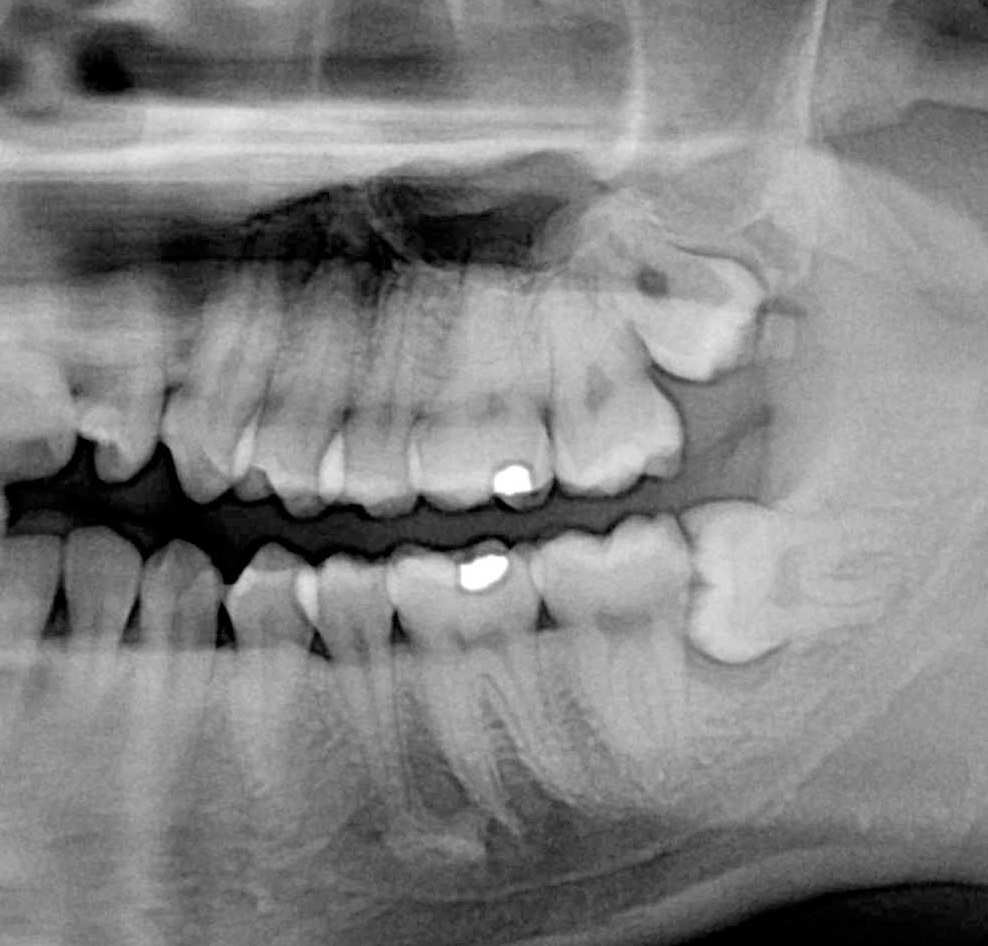

NewTom Giano

Jedná se o nejnovějším přístroj ze skupiny dentálních hybridních CBCT (3D) + 2D (pan i ceph) systémů. Opět umožňuje na základě jediného snímkování vytvořit všechny typy RTG zobrazení, které jsou pro lékaře potřebné. Používaná technologii tzv. „kuželového paprsku“ a speciální senzory pro minimální zátěž při snímkování pacienta.

Vyšetření pomocí tohoto přístroje (nebo

3D DVT - NewTom) a získaná data používáme

pro každou implantaci, dále ve stomatochirurgii (zlomeniny čelistí, zuby moudrosti, cysty, onemocnění čelistního kloubu), ortodoncii (retinované zuby, nadpočetné zuby), parodontologii atd.